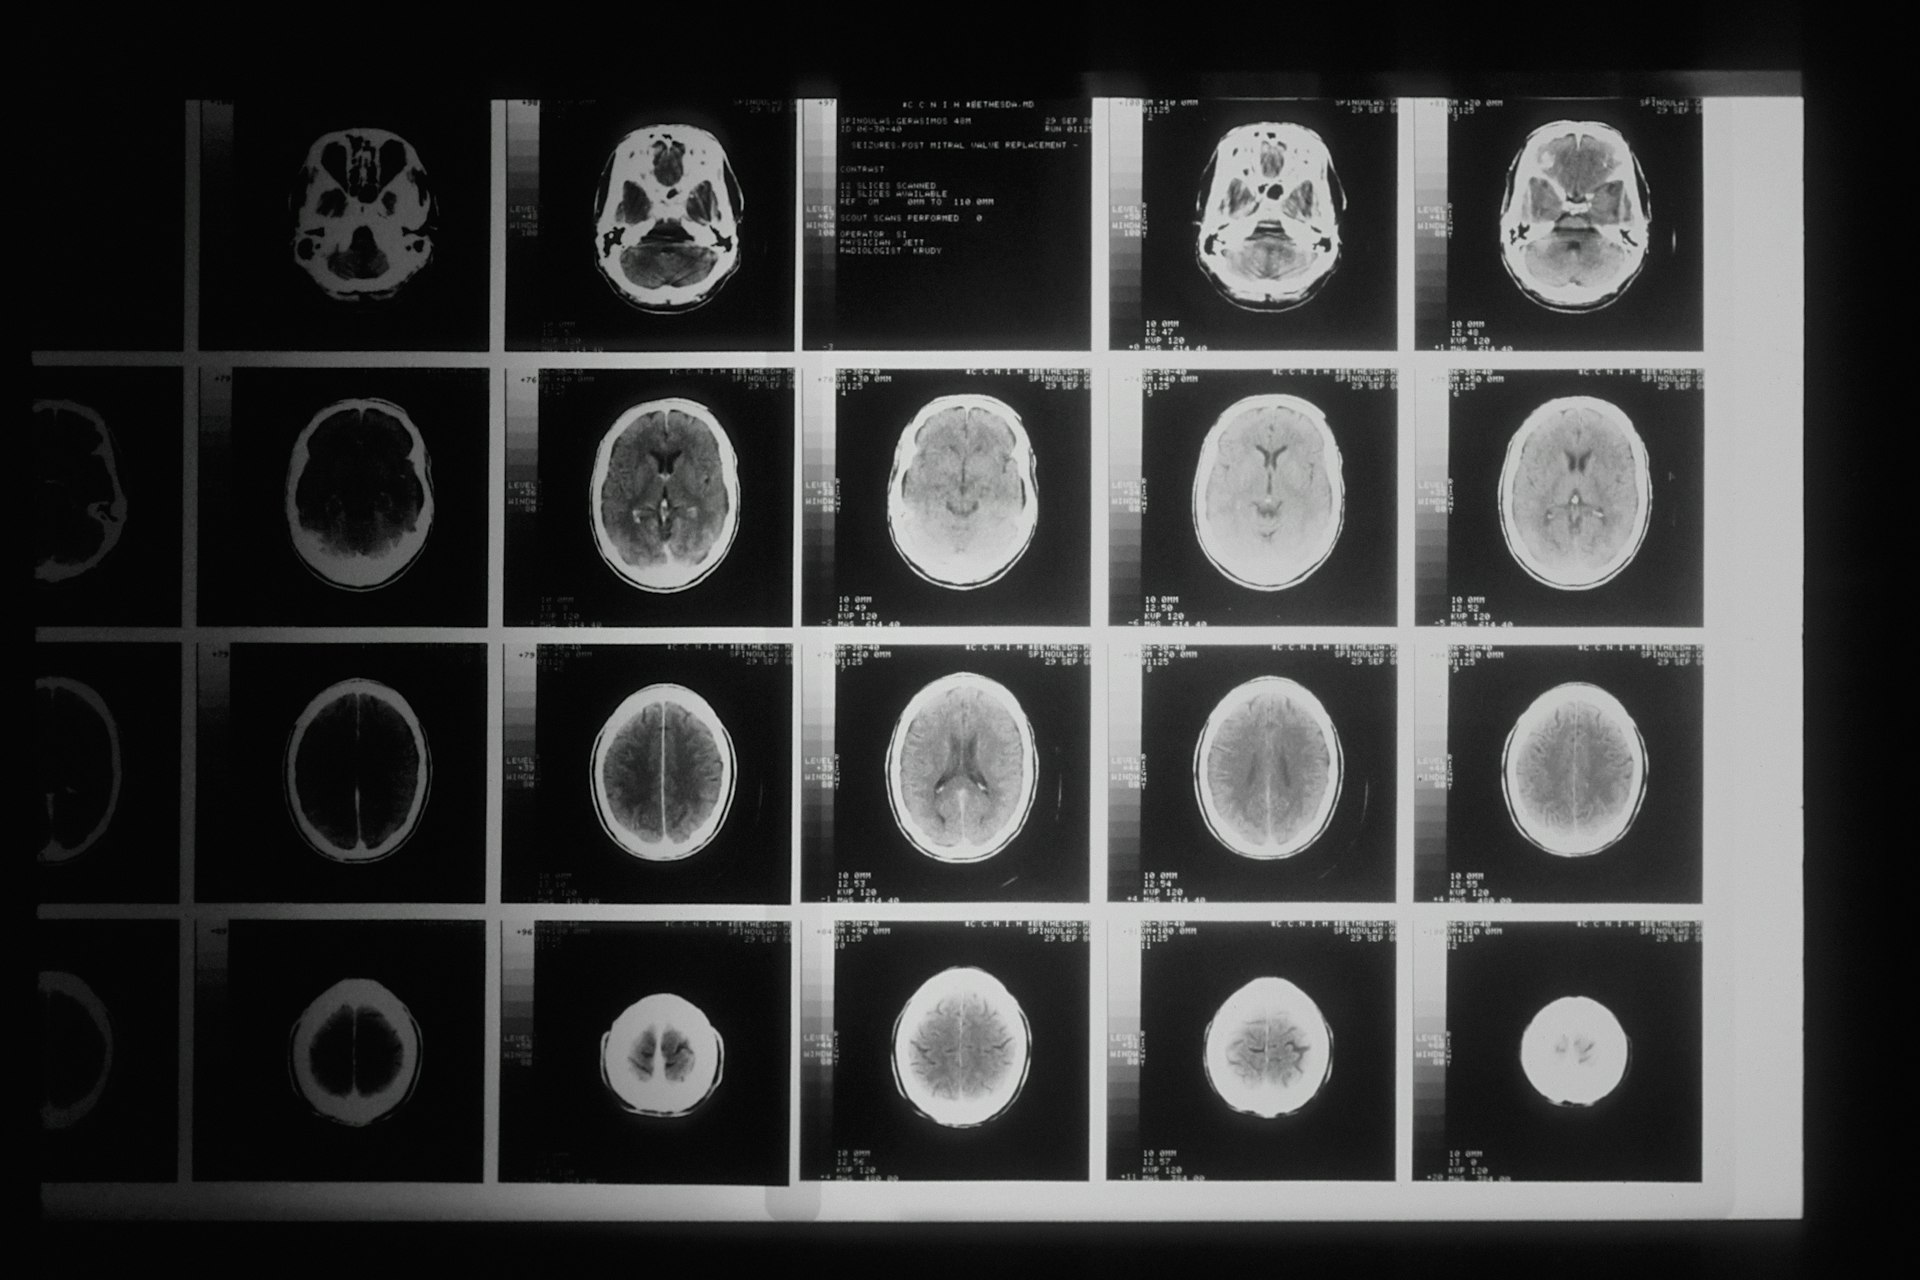

MRI snímek mozku — ilustrační

MRI s kontrastem, audiometrie a vestibulární vyšetření určují přesný rozsah onemocnění.